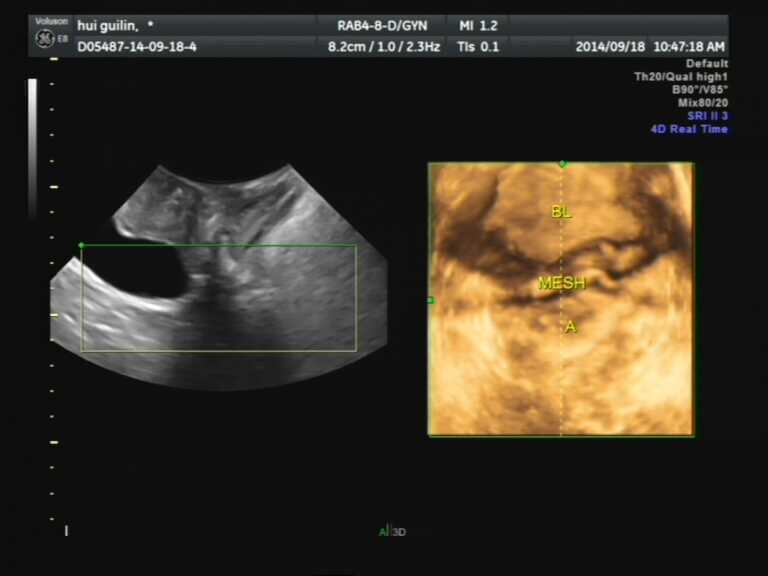

特别是随着三维、四维超声成像的发展,使盆底超声更加动态和立体化。所谓四维成像就是动态三维成像,能够对整个盆底建立非常好的三维容积断层图像,与MRI图像有很好的一致性。另外,盆底超声另一大优势是对盆底手术后效果与患者术后恢复情况追踪,盆底手术后的补片及吊带,在MRI下不能显示,而在盆底超声下可较清晰显示。吊带放置位置是否合适,补片位置大小,有无折叠,挛缩及侵蚀等并发症出现,术后有无压力性尿失禁及盆腔脏器脱垂的复发都可以通过盆底超声进行评估。因此盆底超声检查是盆底手术病例术前必备的检查,也是术后随访的唯一影像学手段。

对于盆底术后患者,盆底超声的优势明显,可以帮助评估预后,对于失败病例协助寻找失败原因。例如,压力性尿失禁术后排尿障碍,通过盆底超声可以看到吊带位置,是否过高过紧,需要调整,还有的患者术后尿失禁无缓解,通过超声发现吊带过低过松,不能起到相应的作用,国外文献报道,超声下吊带位置最好是在中段及近段尿道,在膀胱颈位置及远段尿道的吊带术后复发率相对高。盆腔脏器脱垂患者术后补片的位置、形状、大小、有无折叠、侵蚀等都是通过盆底超声可以看到的。但是盆底超声也有一定的局限性,例如患者不会做缩肛及Valsalva动作,不能得到更加准确的数据来评估,还有就是对于脱垂严重的患者,已经完全脱出至阴道外了,超声探头不能完全覆盖盆底,也会影响盆底超声的结果,不能真实的反应脱垂程度,因此盆底超声检查不能取代临床评估,只是为临床诊断提供额外信息。

补片术后失败,膀胱膨出

吊带术后